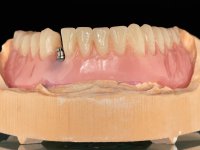

Two dental implants were planned in the CBCT scan, in the area of the inferior canines. The dental extractions were performed and, simultaneously, the alveolar crest was flattened and the implants were placed. Three issues were considered while implant placement: parallelism of the axis, same height of the implant’s neck, and same position in the coronal plan. This 3D insertion is essential to have a good retention of the overdenture in the future. Patient’s removable denture was fixed in the dental lab, to include the extracted teeth, and a soft-tissue relining was done over the healing abutments. After the osseo-integration period, a first impression was done with an open-tray and a doble-mix technique. This dental impression allowed the production of screwed wax-rims and an individual tray for a functional impression. A second impression, final, was done with an individual tray with a monophasic silicone. The occlusal wax-rims were correct in the mouth according to the full denture guidelines. Special care was taken with the occlusal vertical dimension and the support in the soft-tissues. A silicone bite registration material was used to better defined the intermaxillary relations. Teeth set-up was done in the dental lab with the selected tooth color. Due to the fact that the base was screwed to the dental implants, the teeth set-up was functionally evaluated in the mouth. Another silicone bite registration material was used to allow final occlusal adjustments. Finally, the locators were screwed and the retention nylons were selected according to the patient needs.